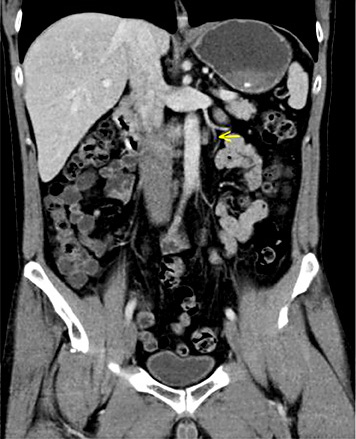

4th patient: this 37-year-old patient had left-sided orchiectomy for a presumed occult germ cell tumour. Histologically, only germ cell neoplasia in situ (TNM: pTis) was found in the specimen. CT revealed a 1.8 cm lymphadenopathy in the para-aortal template. All of the classical serum tumour markers were negative. As histopathologically no invasive GCT was found in the left orchiectomy specimen, the lymphadenopathy was considered unspecific corresponding to a CS1. Accordingly, the patient was put on a surveillance schedule. Four months later, the lymphadenopathy had slightly increased (Fig. 3). Therefore, a laparoscopic lymphadenectomy was performed. Histologically, the specimen revealed a pure seminomatous metastasis. The patient received 3 cycles of BEP chemotherapy subsequently. Before orchiectomy, the miR371a-3p serum level was RQ = 74.4 and it was found to decrease to RQ = 20.4 three days postoperatively, thus clearly lying in the supra-normal range. Prior to lymphadenectomy, the level had increased to RQ = 58.5 and it dropped to RQ = 0.0 after surgical excision of the node to remain there during the later course.